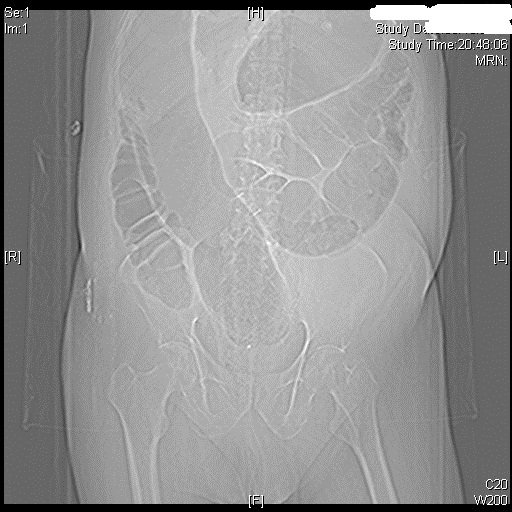

From radiopaedia.org

Ogilvie syndrome Image Ogilvie Collision Body shops, auto glass services. we're fully equipped with all the automotive body repair tools, equipment, and skilled labor to deliver the best service to you. ogilvie collision is a reputable auto body repair shop in ogilvie, mn, specializing in collision repair services. oglivie collision auto body & restoration is open mon, tue, wed, thu, fri. Ogilvie Collision.